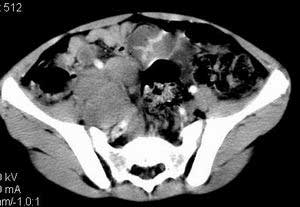

| 患者,男,9岁,因右下腹包块入院,血象不高,不规则发热,常超40度。 平扫: ![]() ![]() ![]() ![]() ![]() ![]() ![]() ![]() ![]() ![]() ![]() ![]() ![]() ![]() ![]() ![]() ![]() ![]() 增强: ![]() ![]() ![]() ![]() ![]() ![]() ![]() ![]() ![]() ![]() ![]() ![]() ![]() ![]() jiajie发言:骶椎右前区不规则软组织肿块,边缘光整,密度均匀,增强后均匀强化,右腹股沟区可见肿大淋巴结,临床有时发热,考虑淋巴瘤,儿童盆腔肿瘤应与神经母细胞瘤和横纹肌肉瘤鉴别。 longzhanghui发言:印象:盆腔右后壁不规则软组织肿块,并向前延伸.似为多个肿块融合,呈中等强化.初步考虑淋巴瘤. 听蝉观竹发言:右侧髂内、外组淋巴结肿大,从其形态和融合的情况看,同意大家意见-----考虑恶性病变,但是9岁男孩还要注意检查睾丸情况,有无隐睾? 常常类似情况是隐睾发生精原细胞瘤淋巴结转移,这个病例也要注意这一点!!! 广东凌发言:大家好,在这里我想说一下个人观点,我建议上传图片的同志能否辛苦一点就是把病史和图片都上传完整一点,比如这个病人的腹膜窗,并且这个病人的肠道的准备也是不怎么好,就从现有的质料看:病灶属于淋巴结肿大当无大的争议,有融合趋势,其内无坏死,边缘强化为主,故考虑:淋巴瘤!建议用腹膜窗看一下和肠道的关系! 阿圣发言:病灶属于淋巴结肿大当无大的争议,有融合趋势,其内无坏死,边缘强化为主,故考虑:淋巴瘤 结果是:淋巴瘤 病例来源:ct762。由宁静致远发布: http://www.radinet.com.cn/forum_view.asp?forum_id=4&view_id=2182 |